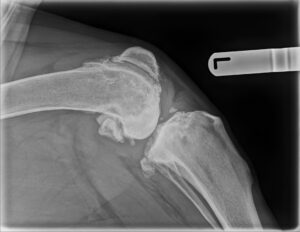

October 2023